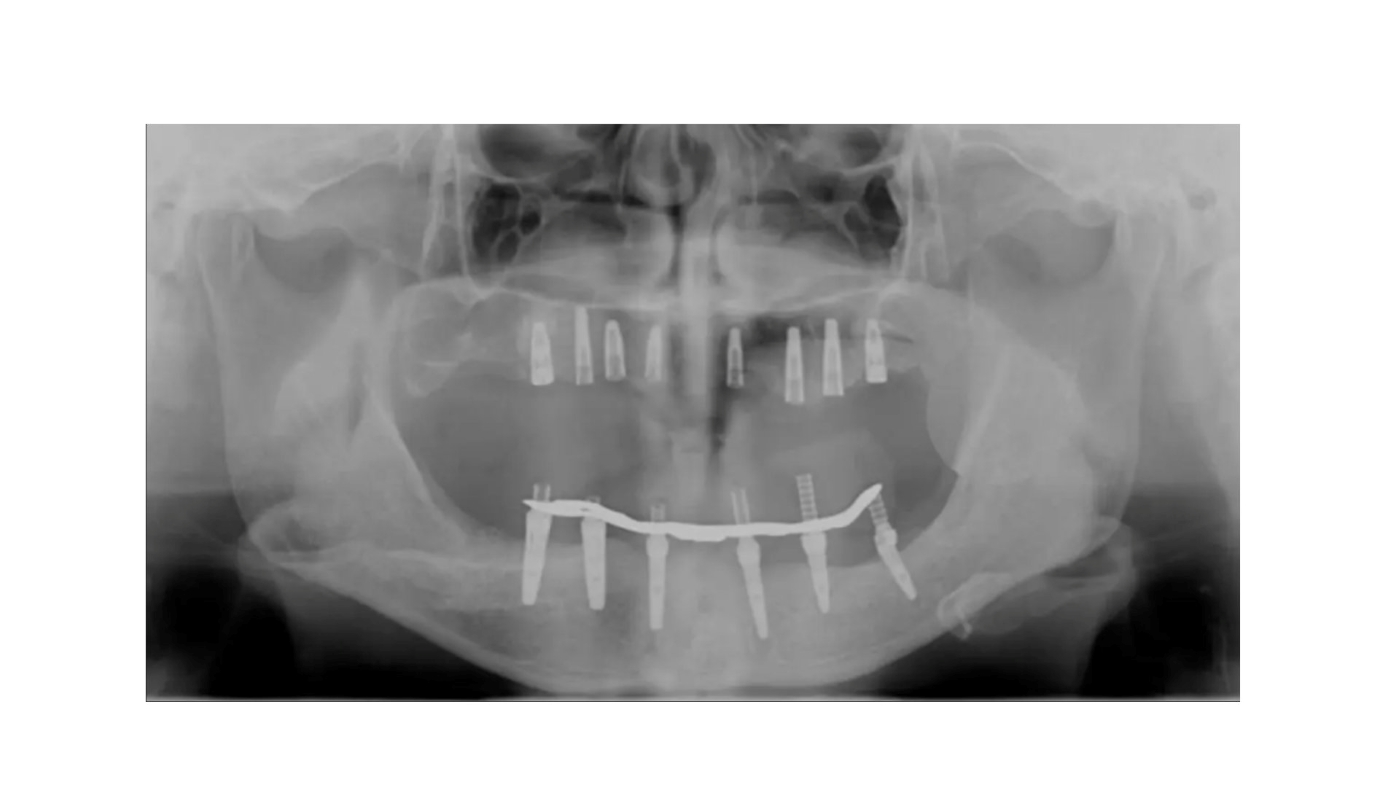

多数歯欠損のインプラント治療の症例(うえだ歯科)

| 主訴 | 歯がグラグラで噛むことができない。インプラントをして欲しい。 |

| 治療内容 | 歯周病で骨の吸収が重度で保存不能なため抜歯、仮の入れ歯を作り、6ヶ月の抜歯窩の治療の後に、インプラントのCTによる診査診断を行い、下顎に6本インプラント埋入と同時に仮歯を入れる。その後、上顎は8本のインプラント埋入と同時に仮歯を入れる。左右上6はソケットリフトによる上顎洞拳上術を行う。その後免荷期間6ヶ月待ってセラミックを用いた上部構造作製、装着しメンテナンスに移行する。 |

| 治療費 | 9,000,000円(税込) |

| 治療期間 | 2年3ヶ月 |

| 治療回数 | 90回 |

| 想定されたリスク | 重度の歯周病により無歯顎になったため、プラークコントロール不良による、術後のインプラント周囲炎が懸念される。歯冠の部分はセラミックなため欠ける可能性がある。 |